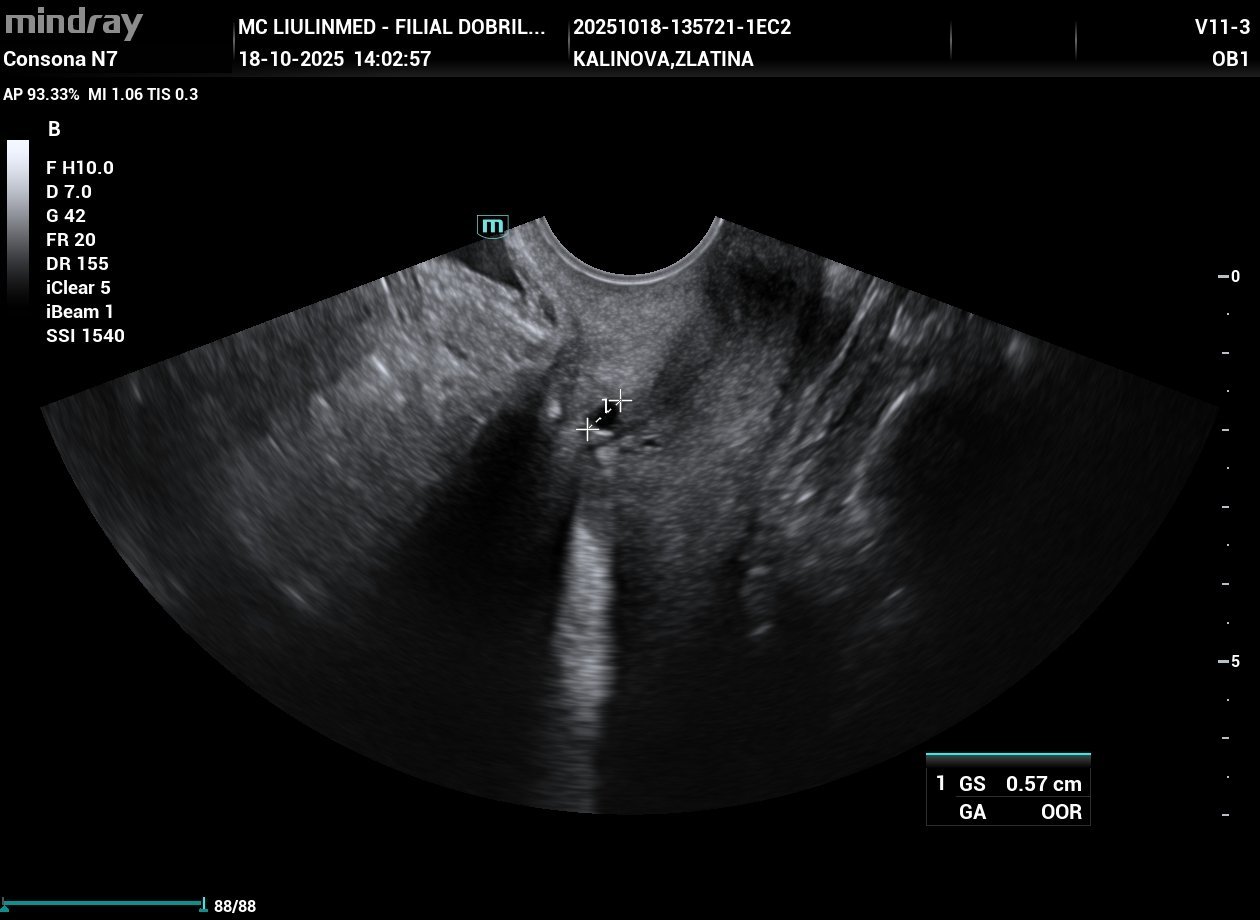

На първата снимка пише, че има един гестационен сак с размер 0,57 см. На втората снимка са яйчниците. На третата е измерена дебелината на ендометриума/маточната лигавица.

На първата снимка пише GS, което е Gestational Sac (гестационен/плоден сак).

Размерите му са 0,57 см.

В същото време обаче не е определен срока на бременността - GA/Gestational Age (OOR - Out of Range), което е странно. Възможно е да отговаря на (прекъсната) много ранна бременност, под 4гс. 5-6мм гест. сакче отговаря точно горе-долу на 3-4гс., но не знам дали толкова рано може да се отчита/брои от ехографа.